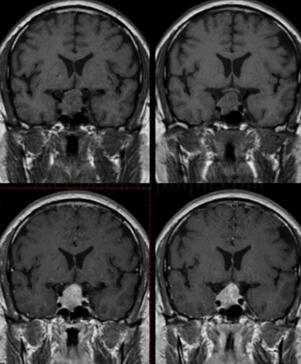

图1 垂体体积增大,大小约2.7cm×2.1cm,并向鞍上生长,垂体柄及视交叉受压移位,第三脑室受压。增强扫描示垂体不均匀强化,内可见低信号区。病变向两侧生长累及海绵窦